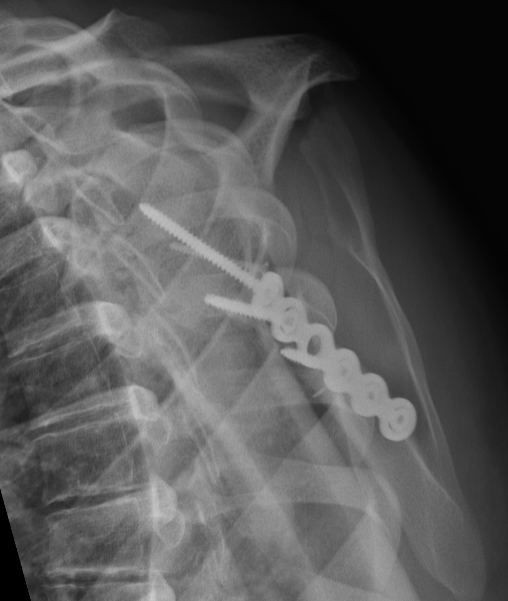

![]() |

Medial displacement

Angulation

Glenopolar angle

Definition

- line connecting the superior and inferior glenoid fossa

- line connecting the superior pole of glenoid and inferior angle scapula

- normal 30 - 40 degrees